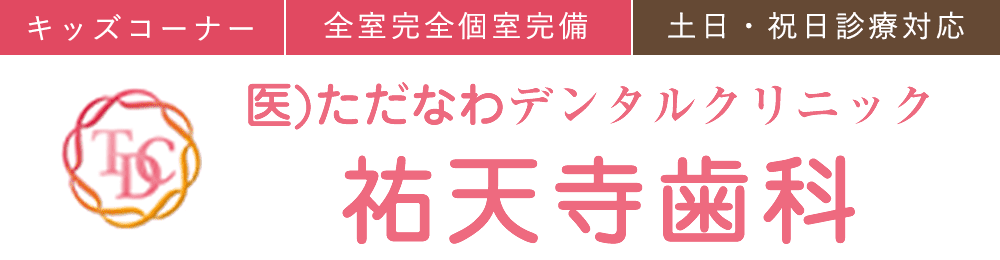

こちらの患者さまは奥歯が割れてしまったが放置をしており、痛みが出てきたとの事で御来院されました。

CT写真を撮影し確認したところ、歯を保存する事ができなかったので、治療方針の種類を相談したところ、入れ歯は嫌という事でインプラント治療を行う事になりました。費用の関係で、1本の埋入に決定しました。

感染を起こしている範囲が広かったため、まずは親知らずから割れた歯を含む3本の奥歯を抜歯しました。また、当該歯は下歯槽神経との距離が近かったため、まずはじめに骨造成を単品で行いました。